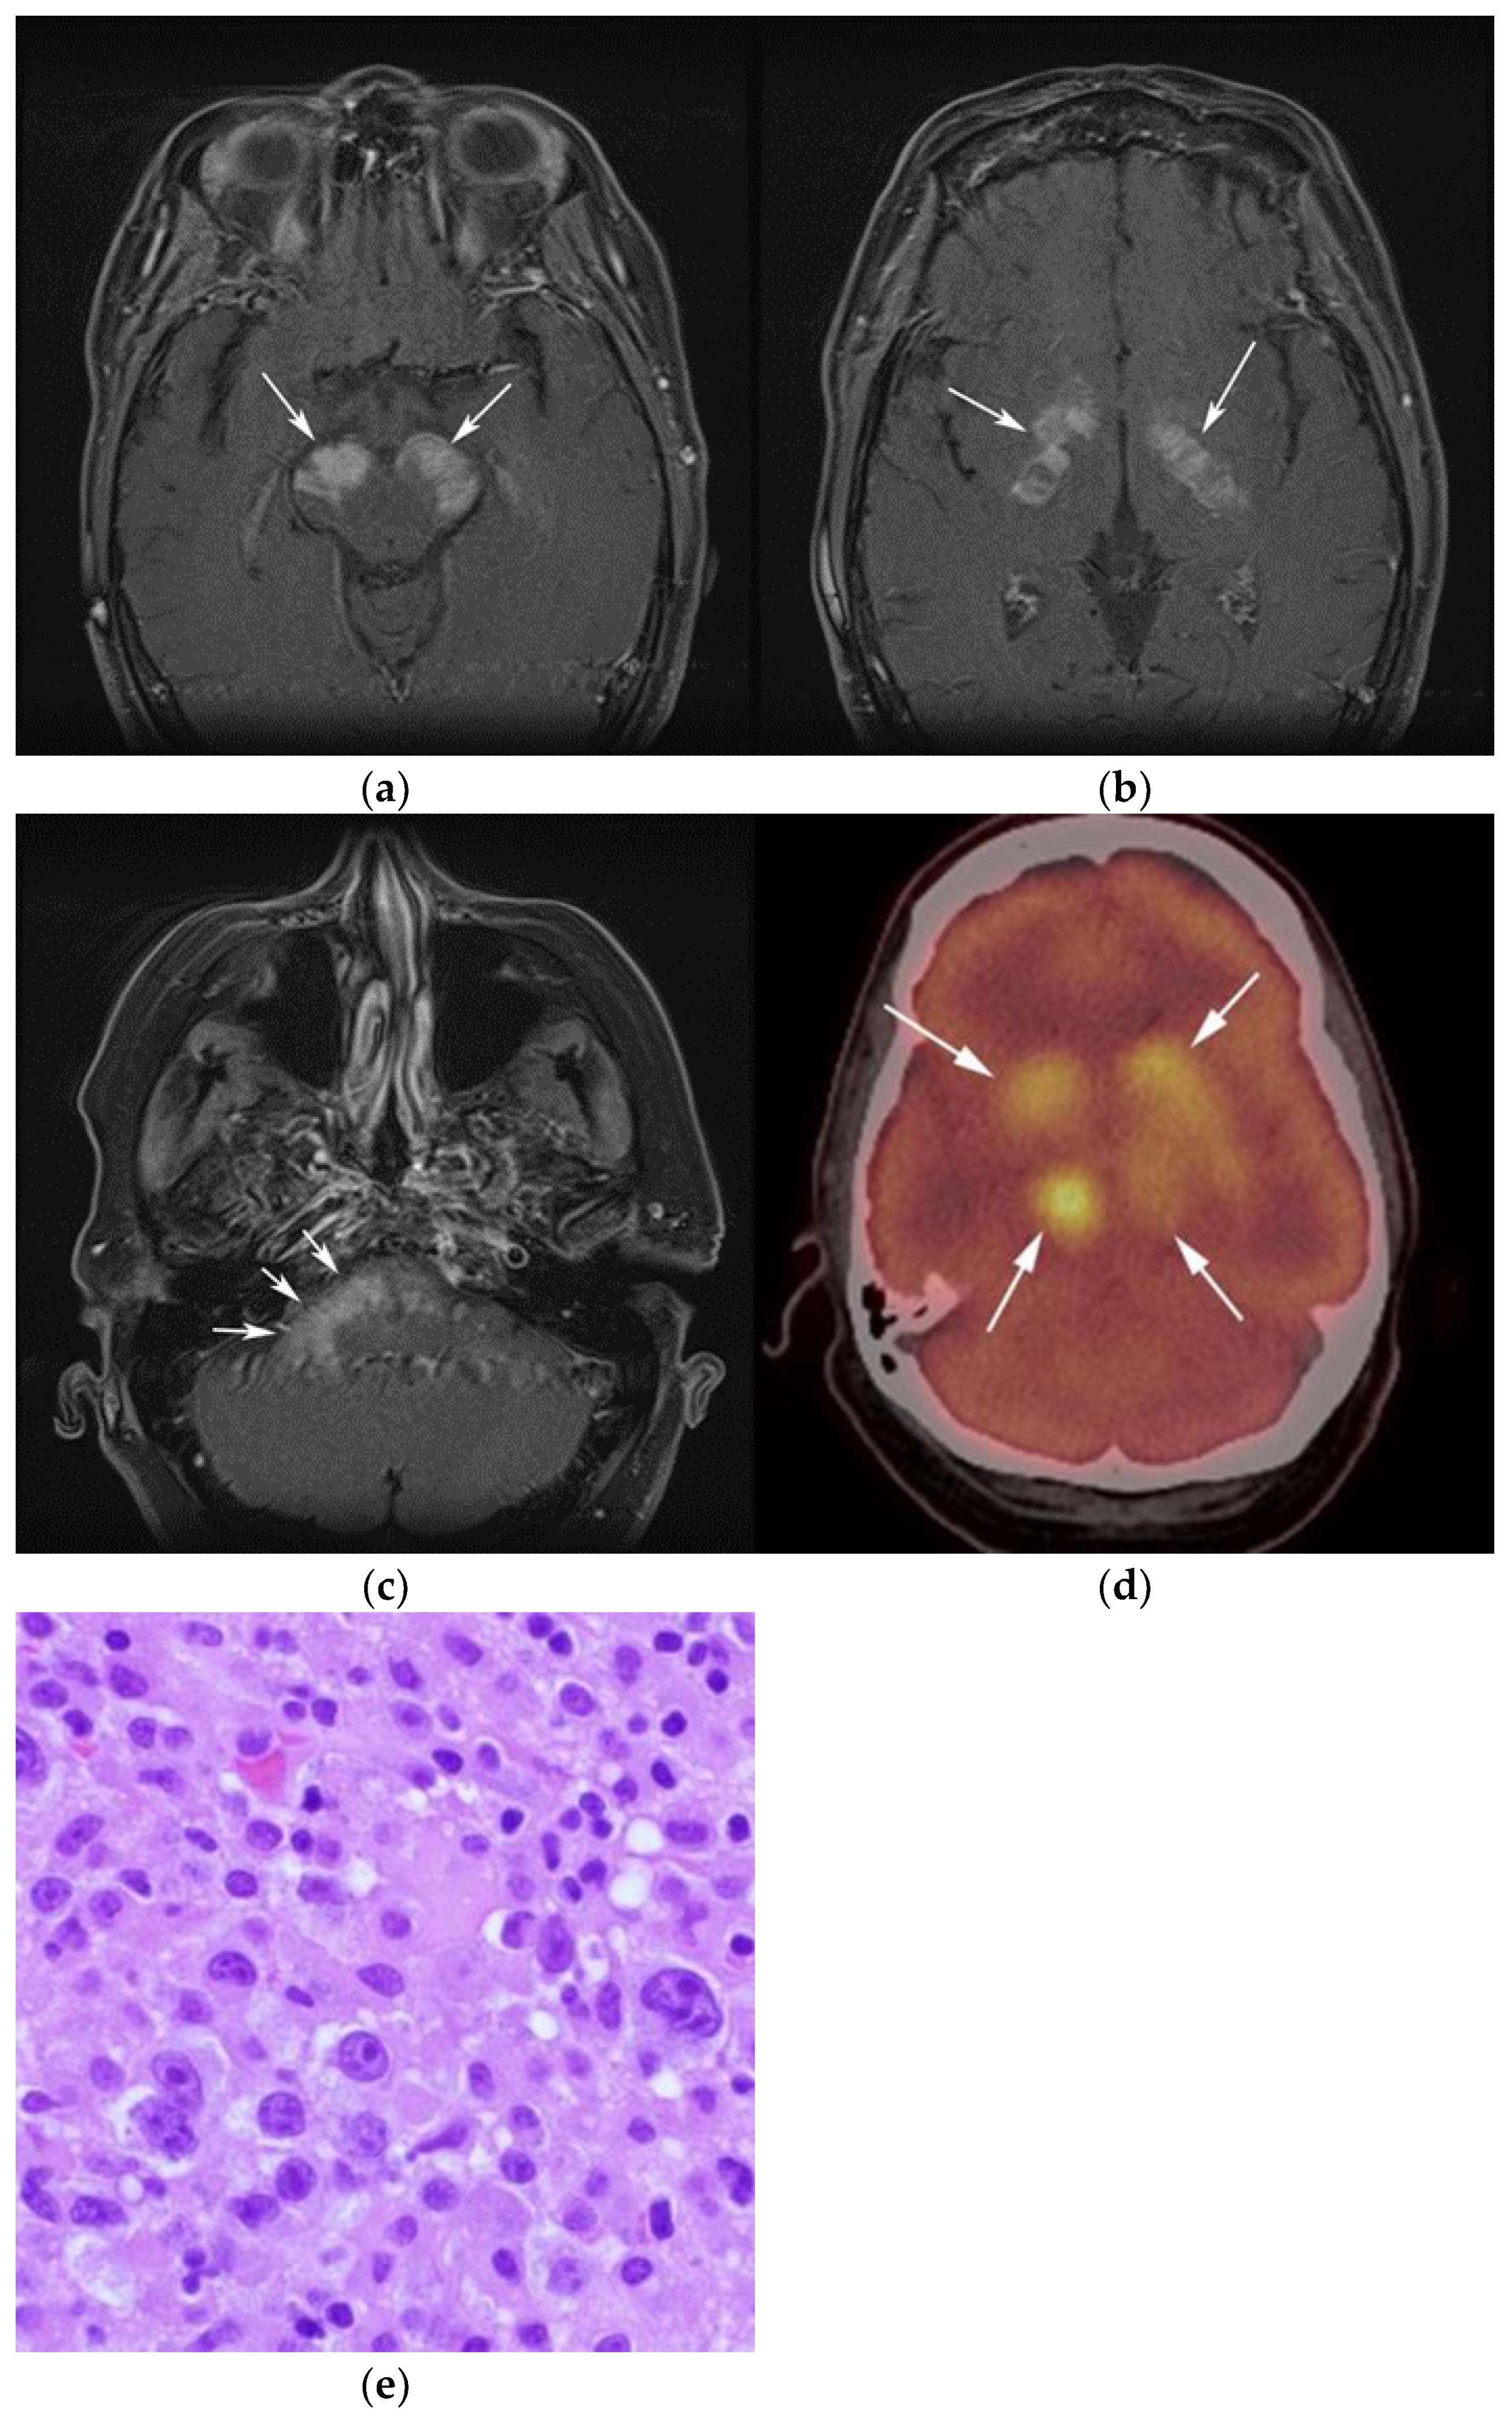

Figure 3.

Same MRI series. (a) Axial post-contrast MRI image shows lesions extending caudally to involve the bilateral superior cerebral peduncles and anterior aspect of the mid-brain. (b) Axial MRI T1 post-contrast fat-saturated images show involvement of the posterior limb of the internal capsule and the thalami bilaterally (white arrows). (c) Extension along the lateral aspect of the pons, dentate nucleus, and the middle cerebellar peduncles (white arrows). (d) Axial FDG fused PET/CT image shows increased activity in the aforementioned lesions. Additional hypermetabolic lesions are seen along the course of the corticospinal tract (white arrows). Imaging findings and pattern of involvement are consistent with lymphomatosis cerebri. (e) H&E section shows a tumor composed of large and pleomorphic cells with intermingled small lymphocytes. Primacy CNS lymphoma typically demonstrates an angio-centric predilection. (Original magnification 400×, H&E stain). Other differential diagnoses include a vasculitic process, toxic or metabolic encephalopathy, paraneoplastic syndrome, or acute disseminated encephalomyelitis. Biopsy showed a large non-cohesive B-cell lymphocyte population consistent with LC.